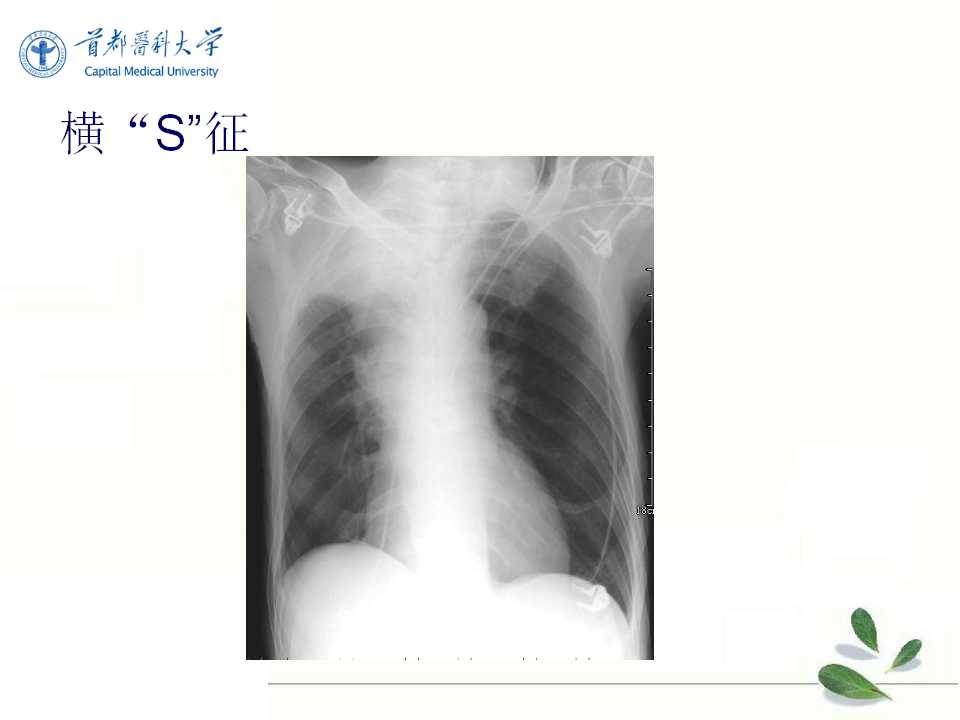

肺癌的影像学检查